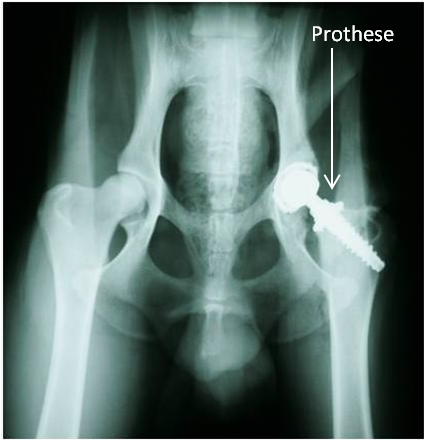

"Tyler", ein Dobermann-Mix, wurde am 18. August 2011 vom Nümbrechter Tierschutzverein "Menschen für Tiere e.V." in der Praxis vorgestellt mit dem Hinweis, er habe große Probleme mit seiner Hüfte und könne nur sehr schlecht laufen. Er war abgemagert bis auf die Knochen, lethargisch und litt sichtbar unter Schmerzen. Tyler zeigte einen deutlichen Muskelabbau und einen Hochstand des rechten Oberschenkels. Bei der Ganguntersuchung ist uns eine starke Lahmheit dieses Beines aufgefallen. Der Bewegungsumfang des Hüftgelenkes war deutlich eingeschränkt und bei der Streckung zeigte der Hund Schmerzen. Daraufhin haben wir eine Röntgenuntersuchung durchgeführt, wobei sich herausstellte, dass die Hüfte luxiert war, mit anderen Worten: der Oberschenkelkopf saß nicht in der richtigen Position. In einer funktionierenden Hüfte sitzt der Oberschenkelkopf in der Pfanne (s. Abb. 1). Bei Tyler saß der Oberschenkelkopf oberhalb der Pfanne. Er wies diese Veränderung seit langer Zeit auf, so dass der Oberschenkelkopf eine Pseudopfanne im Becken gebildet hatte (s. Abb. 2).

Der künstliche Hüftgelenkersatz wird in der Tiermedizin seit mehr als 30 Jahren zur Behandlung von Hüftgelenkerkrankungen und -Traumata verwendet. Im Grunde werden bei diesem Verfahren Oberschenkelkopf und Pfanne durch eine sog. Oberschenkelkopf- und Pfannenprothese ersetzt. Es gibt verschiedene Modelle von Prothesen. Tylers Oberschenkelkopfprothese besteht aus Titan, die Pfanne besitzt eine Außenhülle ebenfalls aus Titan und eine Innenbeschichtung aus Polyäthylen (s. Abb. 3).